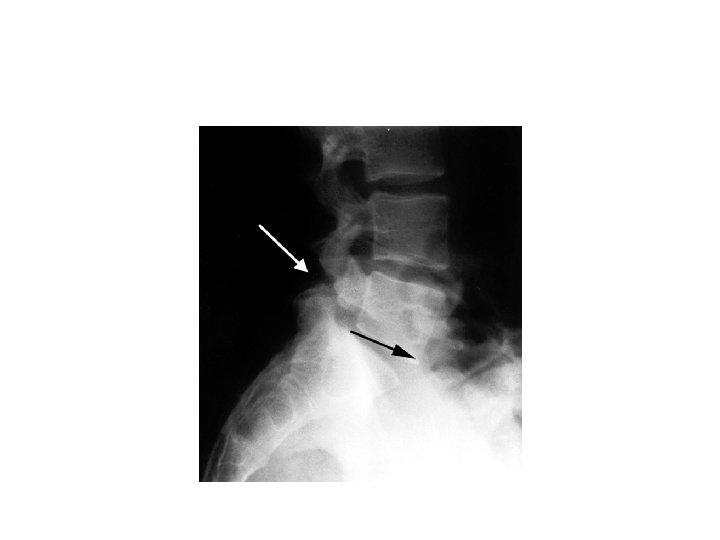

• Imaging studies : - X-ray : AP radiographic findings are usually normal in spondylolysis. The oblique views ( Rt. And Lt ) are particularly screened for the "Scotty dog" lesion in the pars interarticularis. The pars defect is represented by the collar on the Scotty dog. - ( 99 m Tc) / SPECT bone scan : superior to CT/MRI : these scans can aid in establishing the acuity of the lesion or in identifying the site of the problem in an athlete with negative plain radiography results but whose clinical course is suggestive of a pars interarticularis fracture.

• Imaging : - X-ray : AP , lateral , oblique * on lateral view : forward slip is evident. * on oblique view : gap in pars interarticularis. - MRI : to evaluate impingement of neural elements. - CT : for bony pathology. - CT myelogram : when MRI contraindicated.